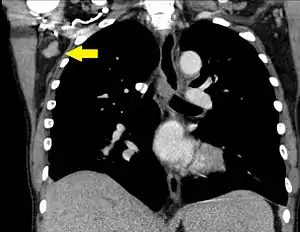

![]() | |

| A CT scan of axillary lymphadenopathy in a 57-year-old man with multiple myeloma. | |